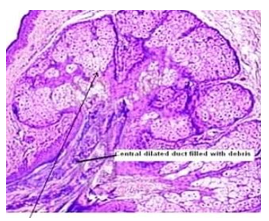

Upon microscopic examination, mature sebaceous glands appear aggregated subjacent to mucosal epithelium. The visible sebaceous glands appear in continuum with superimposed cutaneous surface and are devoid of associated hair follicles [6,7]. Nevertheless, a ductal communication with superficial epidermis may be absent [6,7].

The morphological countenance is akin to normal cutaneous adnexal sebaceous glands. Superimposed stratified squamous epithelium demonstrates parakeratosis and exhibits subjacent lobules of mature sebaceous glands [6,7].

Figure 3: Fordyce's granules exhibiting enlarged sebaceous glands imbued with lipids and a superimposed stratified squamous epithelium (11).